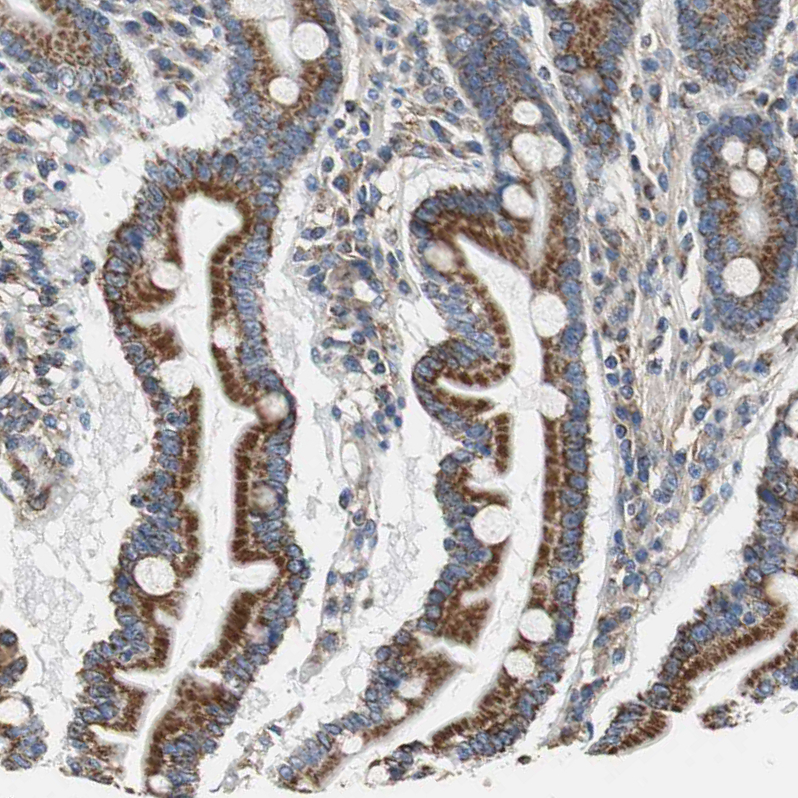

Immunohistochemistry analysis in human duodenum and pancreas tissues using HPA006311 antibody. Corresponding GSTK1 RNA-seq data are presented for the same tissues.